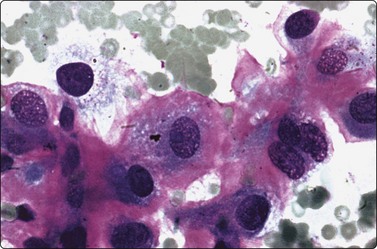

The cytological appearance of conventional ES is distinctive. Smears are generally highly cellular and are composed of both single cells and groups of loosely cohesive cells. The cells are fragile and naked nuclei as well as a faint gray–blue (MGG) background of detached cytoplasm are commonly seen. There is a characteristic mixture of two types of cells. One has abundant pale cytoplasm with vacuoles or large clear spaces, rounded or ovoid nuclei with finely granular chromatin and 1–3 small nucleoli (‘large light cells’). The other has scanty cytoplasm and irregular nuclei with dense chromatin (’small dark cells’). The two types of cells are most clearly distinguished within groups or clusters of cells, the small dark cells are interspersed, often as small molded groups, between large light cells (Fig. 16.31A). Rosette-like structures without a fibrillar center are occasionally present (Fig. 16.31B,C). The cytoplasmic vacuoles or clear spaces correspond to large deposits of glycogen (Fig. 16.31A).

image image image

Fig. 16.31 Ewing’s sarcoma

(A) A mixture of cells with larger pale-staining nuclei and cells with smaller and darker nuclei; note the cytoplasmic vacuoles and clear spaces in the pale cells (MGG, HP); (B,C) Rosette-like structure; nuclear chromatin and nucleoli more clearly seen in H&E than in MGG (A, H&E, HP; B, MGG, HP).

In atypical ES and PNET the cellular and nuclear atypia is more marked than in conventional ES. Rosette-like structures are more common and the distinction between large light and small dark cells less obvious, especially in PNET, and cells with thin cytoplasmic processes as well as rhabdomyoblast-like cells are present (Fig. 16.32).

image image

Fig. 16.32 ES/PNET family of tumors

Distinction between large light and small dark cells less obvious in PNET than in conventional Ewing’s, and cells with thin cytoplasmic processes (A) and rhabdomyoblast-like cells (B) are present (A, MGG, HP; B, H&E, HP).